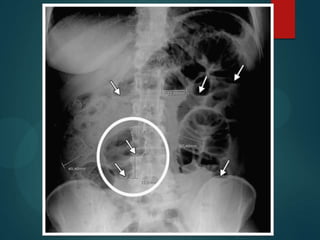

Datos tomográficos:

Es la técnica de elección en sospecha de OI y

estrangulación (S de 83-100% y E de 61-93%) y

otras complicaciones. Sus ventajas son:

- Es rápido

- No requiere contraste oral, debido a que el liquido

retenido intraluminal sirve como un contraste

negativo natural.

- Tiene más sensibilidad para determinar el sitio y la

causa de la obstrucción.

Signos de obstrucción :

Dilatación de asas proximales al punto de obstrucción mayor

de 2,5-3 cm (>2,5 cm aumenta S al 90%).

Grado de obstrucción dependerá del grado de colapso del

asa distal al punto de obstrucción y la cantidad de gas y

líquido retenido proximal

Signo de collar de perlas, signo de las heces, niveles de

contenido liquido heces.

3.45cm   2.86cm

La identificación del punto de transición en una obstrucción del intestino delgado

secundaria a adherencias postoperatorias. TC axial muestra dilatación de asas de

intestino delgado (S). Hay un cambio abrupto en el calibre (flecha) entre las asas

intestinales dilatadas proximales y distales colapsadas asas intestinales (C). El cambio

en el calibre era debido a adherencias.

TC demostrando asas proximales dilatadas y

distales colapsadas (flechas) compatibles con una

OI.

Datos tomográficos: Es latécnica de elección en sospecha de OI y estrangulación (S de 83-100% y E de 61-93%) y otras complicaciones. Sus ventajas son: - Es rápido - No requiere contraste oral, debido a que el liquido retenido intraluminal sirve como un contraste negativo natural. - Tiene más sensibilidad para determinar el sitio y la causa de la obstrucción.

Signos de obstrucción: Dilatación de asas proximales al punto de obstrucción mayor de 2,5-3 cm (>2,5 cm aumenta S al 90%). Grado de obstrucción dependerá del grado de colapso del asa distal al punto de obstrucción y la cantidad de gas y líquido retenido proximal Signo de collar de perlas, signo de las heces, niveles de contenido liquido heces.

La identificación delpunto de transición en una obstrucción del intestino delgado secundaria a adherencias postoperatorias. TC axial muestra dilatación de asas de intestino delgado (S). Hay un cambio abrupto en el calibre (flecha) entre las asas intestinales dilatadas proximales y distales colapsadas asas intestinales (C). El cambio en el calibre era debido a adherencias.

TC demostrando asasproximales dilatadas y distales colapsadas (flechas) compatibles con una OI.